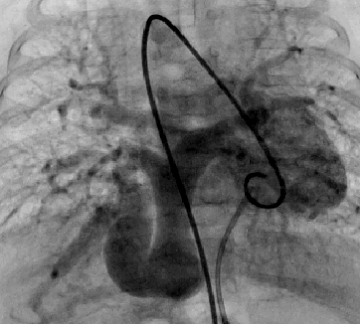

心血管造影

(a)肺动脉闭锁 (b)动脉导管供应肺血

(c)极重度肺动脉瓣狭窄 完全性肺静脉异位引流(心下型)